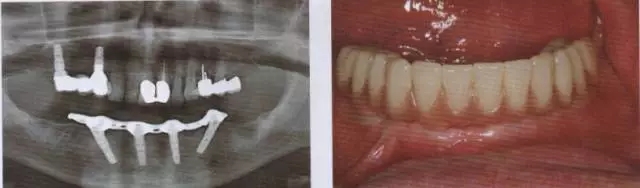

圖13 在取下上部結(jié)構(gòu)后可以看到完全無刺激反應(yīng)的軟組織

圖14 在下頜種植手術(shù)一年后可以看到種植體周圍骨水平穩(wěn)定且拔牙窩形成進一步的骨再生

圖15 在帶入終修復(fù)體后檢查,種植體完全無炎癥